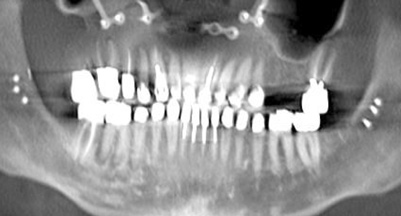

Fig 2. Four vertical machined-surface osseointegrated implants placed in 1983 penetrated the inferior cortex up to 3 mm to 4 mm in depth, immediate postoperative.

Figure 2

Fig 3. At 4 years and 5 months follow-up, reparative bone had formed to the apices of all implants.

Figure 3

The Toronto Conference in 1982, chaired by Professor George Zarb and presented by Professor Per-Ingvar Brånemark, was a seminal event that changed edentulous treatment planning concepts irrevocably. No longer was it necessary to rebuild lost bone through grafting alone in either arch. The severely atrophic mandible, for example, could be treated with as few as four implants used to support a bone-sparing prosthesis through integrated tooth analogs, as demonstrated in Figure 1 through Figure 3. Here, an 81-year-old patient presented with severe mandibular atrophy (Figure 1) from denture wear since a very young age and had a history of being unable to manage a mandibular prosthesis despite numerous attempts at new denture construction. Four vertical machined-surface osseointegrated implants were placed in 1983 by Professor Brånemark, and all four penetrated the inferior cortex up to 3 mm to 4 mm in depth, as shown on the immediate postoperative panoramic film (Figure 2). At 4 years and 5 months, reparative bone had formed to the apices of all implants (Figure 3), and all of them remained in uncompromised function until the patient passed away at age 90.